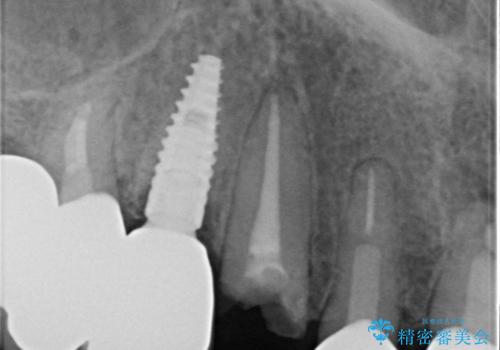

全顎的な治療後に、急遽ニューヨークへ転居されることとなったのですが、治療後から経過観察を行っていた右上犬歯が歯肉縁下に及ぶむし歯のため、クラウンが土台ごと外れてしまったとの連絡がありました。

他の部位にインプラント治療を行っていたことから、こちらの歯に対してもインプラントによる補綴治療を希望されたため、1泊での帰国時に抜歯、インプラント埋入、仮歯の装着を行い、数ヶ月後の帰国時にオールセラミッククラウンの型取りと装着を行う計画としました。

インプラント埋入時は1泊、補綴治療時には3週間ほど日本に滞在していただき、2回の渡航で無事に治療を終えることができました。